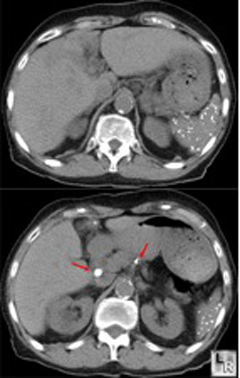

Patient with histoplasmosis showing the classic starry spleen, as well as

two calcified mesenteric lymph nodes (shown by red arrows).

Published with permission from LearningRadiology.com

- Histoplasmosis - Much more than 6 fully calcified granulomas in the spleen. Calcified lesions are larger than those seen in TB. Mesenteric, hilar, and mediastinal lymph nodes may also show calcification.

The movie file below is the CT scan of cadaver 33487. Take a look at the spleen (time= 75, N11). Notice the appearance of the spleen, and the pattern of calcifications. Look now at the abdomen from time= 75-80. Notice how multiple mesenteric lymph nodes are calcified. This presentation of splenic and mesenteric lymph node calcification is most characteristic of Histoplasma capsulatum infection (Histoplasmosis).